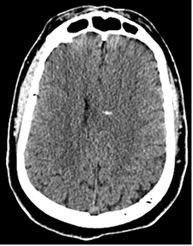

Figures ci-dessus : Accident de moto sur circuit, intubation sur place. Le body-scanner révèle un hématome sous dural supra-tentoriel gauche, de multiples petites contusions cérébrales hémorragiques, une fracture isolée du condyle occipital droit, une contusion du rein gauche avec lame d’hématome sous capsulaire.